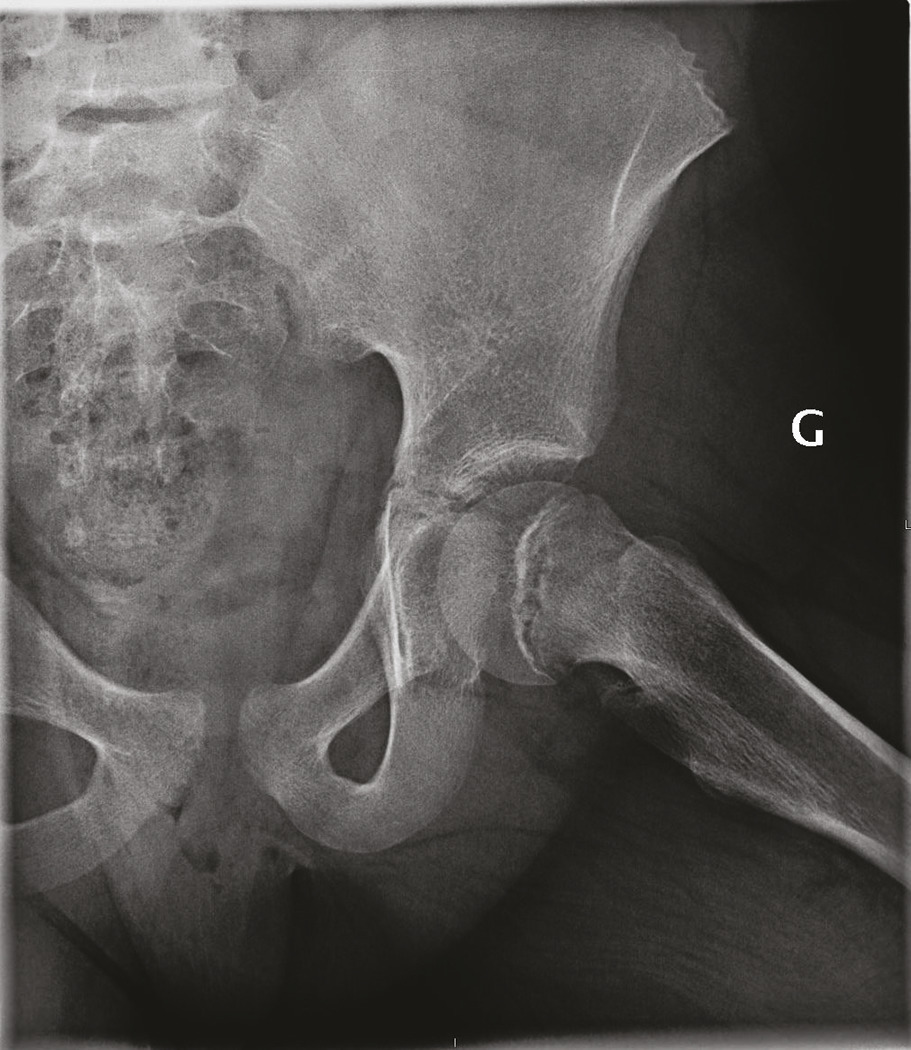

Bascule de la tête fémorale en dedans et en arrière (fig. 1), de cause inconnue, mais liée à une fragilité du cartilage de croissance.

Diagnostic confirmé par radiographie du bassin de face et surtout de profil. En cas de glissement minime : tracer la ligne de Klein, tangente au bord supérieur du col fémoral (elle ne croise plus le pôle supérieur de l’épiphyse ; fig. 1a).